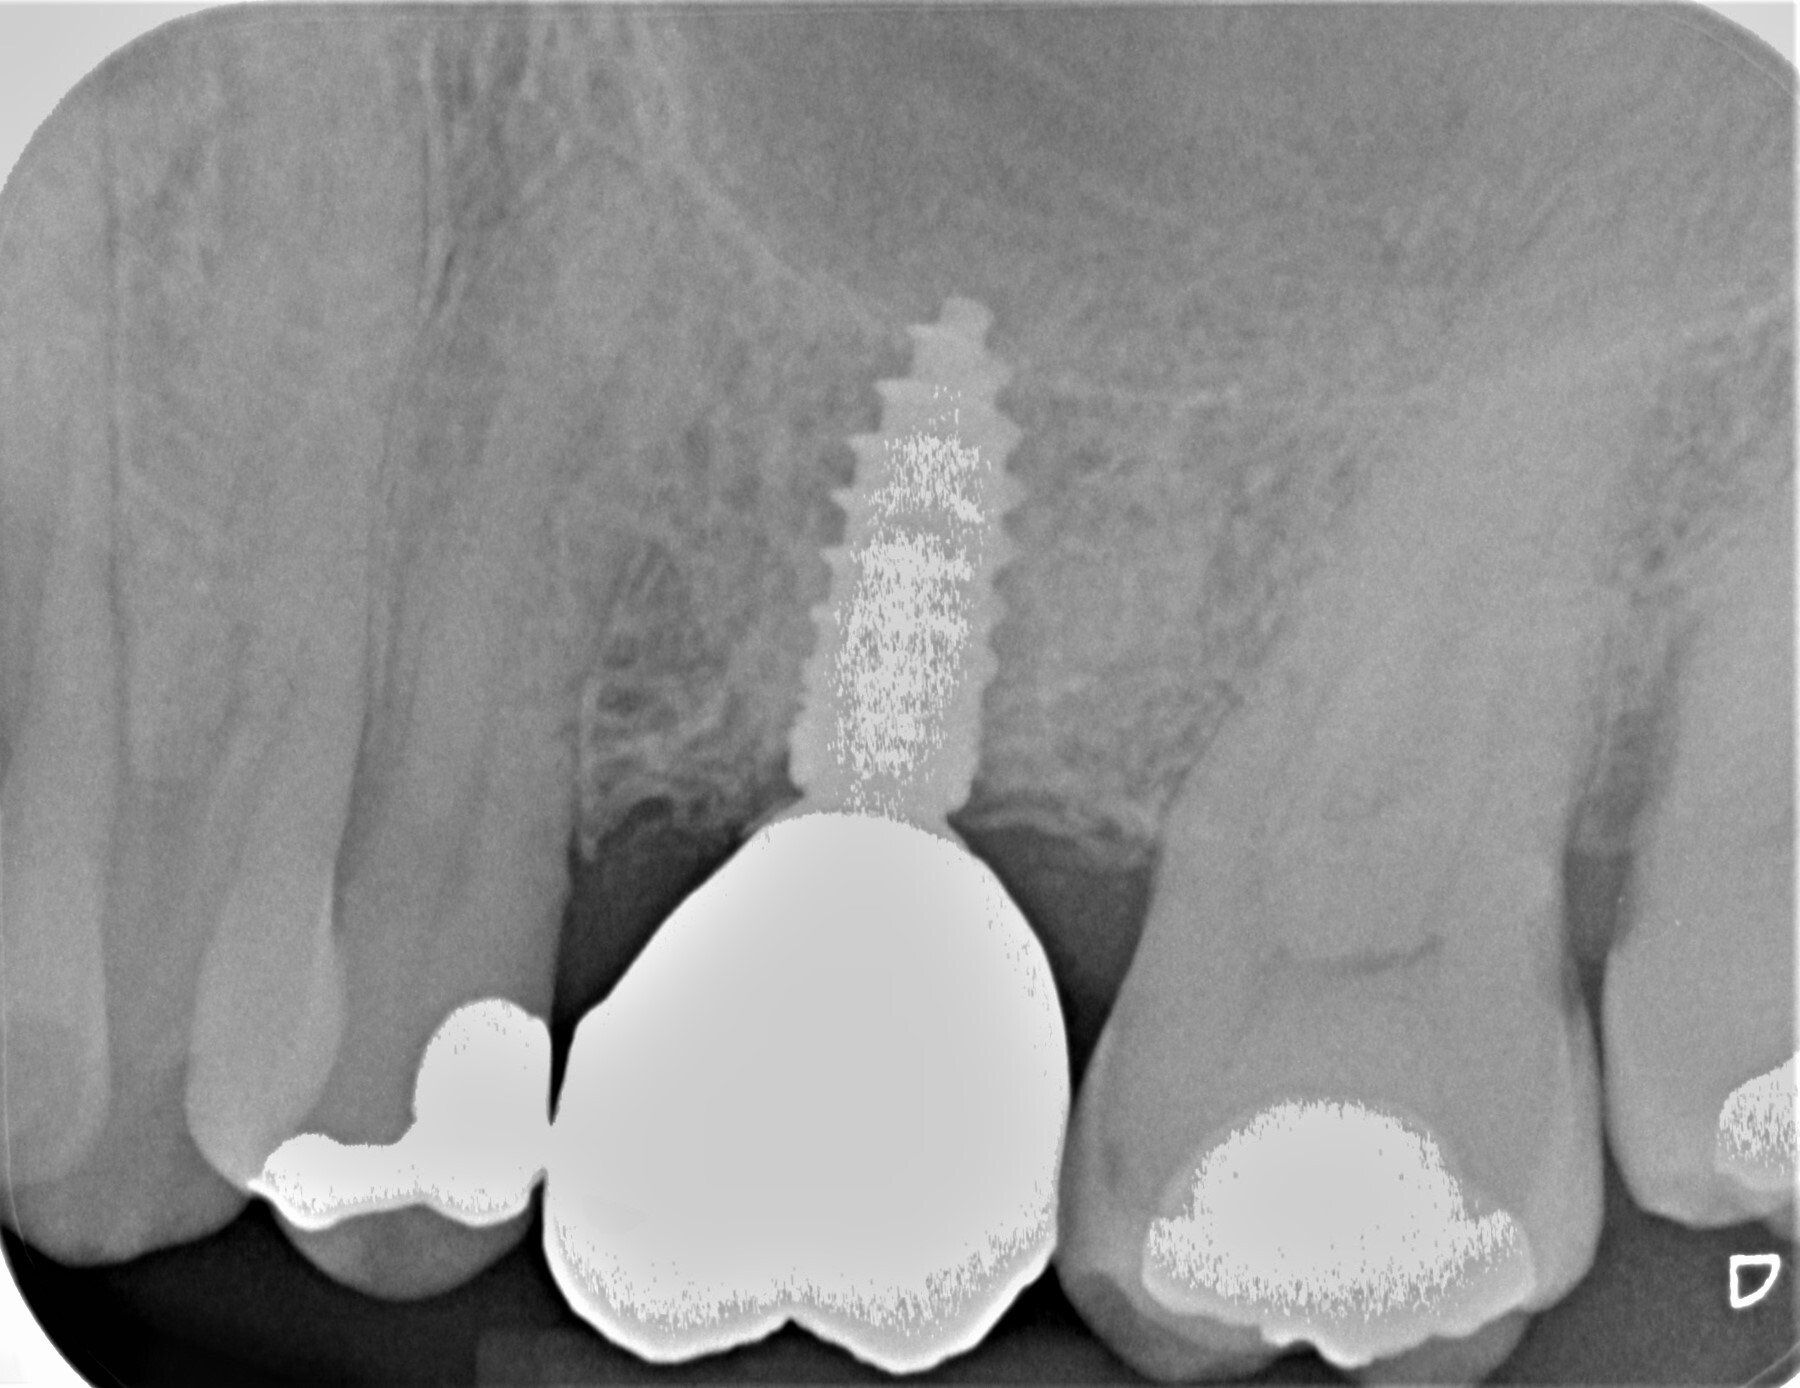

Durch den Verlust des Zahnes wandelt sich der Kieferknochen um. Nach der oberflächlichen Heilung wird das knöcherne Zahnfach vom Körper rasch abgebaut. Knochen ist für den Körper ein "teures" Gewebe, und ohne die funktionelle Kaubelastung durch einen Zahn gibt es für den Körper keinen Grund mehr, das knöcherne Zahnfach zu erhalten. Allein im ersten Jahr nach der Zahnentfernung gehen 50% des umgebenden Knochens verloren! Das ist insbesondere dann von Nachteil, wenn geplant ist, später ein Implantat für den Ersatz des Zahnes zu setzen. Ohne kiefererhaltende Maßnahmen reicht oftmals der nach der Heilung verbliebene Knochen nicht mehr aus, ein hinreichend großes Implantat einzusetzen bzw. dieses auch ideal zu positionieren.

Das Verfahren ist schonend und erfordert keinen zweiten Eingriff. Materialien tierischen Ursprungs werden vermieden. Die Aufbereitung findet direkt nach der Zahnentfernung in unserem Labor statt. Nach ca. 25 Minuten kann das Knochenfach aufgefüllt werden. Der Bereich muss für zwei Wochen geschont und auf der anderen Seite gekaut werden. Es sollte zwei Tage nicht geraucht werden. Alles weitere können wir den Selbstheilungskräften unsres Körpers überlassen.